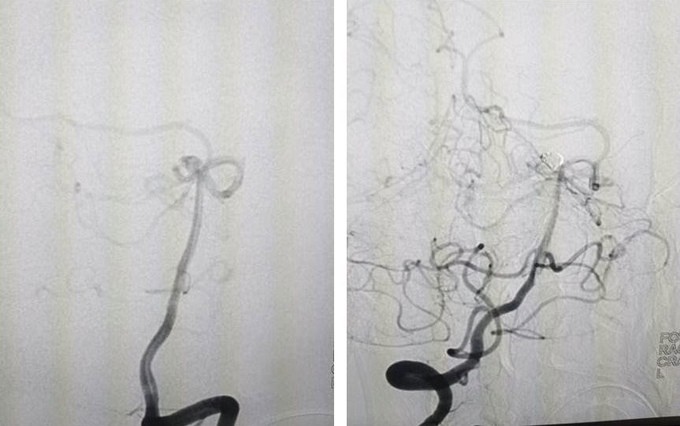

Hình ảnh chụp trước và sau khi can thiệp cho bệnh nhân bị vỡ túi phình mạch mão. Ảnh: Bệnh viện cung cấp

Các bác sĩ can thiệp nút túi phình bằng phương pháp luồn một ống thông nhỏ từ động mạch đùi đưa lên đoạn mạch não bị tổn thương rồi tiếp cận túi phình động mạch não. Sau đó, kíp thực hiện nút mạch bít túi phình bằng vòng xoắn Coil dưới hệ thống chụp mạch số hóa xóa nền (DSA).

Sau ba tiếng can thiệp, kết quả chụp mạch kiểm tra thấy không còn hình ảnh túi phình. Hiện, người bệnh đã có thể ăn uống, tự nuốt được, tiếp xúc tốt, sức khỏe ổn định, chỉ còn đau đầu nhẹ.